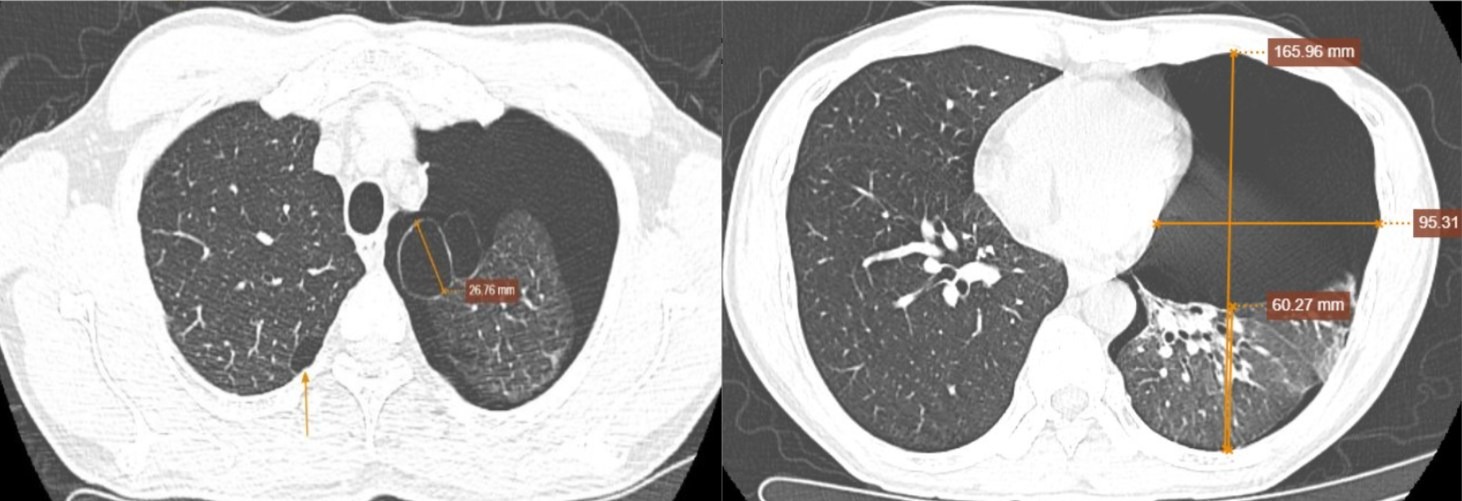

A frequência cardíaca era regular, com 98 batimentos por minuto, a pressão arterial de 140/90 mmHg e a SpO₂ de 95%. A tomografia computadorizada de baixa dose revelou um grande pneumotórax esquerdo, causando colapso pulmonar passivo de até 75%, sugerindo fortemente a ruptura de um cisto de ar.

As imagens também mostraram cistos de ar no lobo superior do pulmão esquerdo e dilatação alveolar adjacente aos septos pulmonares. O ecocardiograma e a ultrassonografia pleural revelaram o coração deslocado para a direita, perda do deslizamento pleural e ausência da linha B.